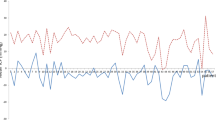

Case example with correlation of ICP changes with valve adjustments

In a 13-year-old boy with posthemorrhagic hydrocephalus after prematurity, chronic headaches were reported. The patient had primarily a paediGAV (9/29 cmH2O) since early childhood and had no shunt revision until the age of 12 years. At this age, he reported about headaches related to activity, more pronounced later during the day rather than in the morning. Thus, the symptoms were interpreted as overdrainage-related headaches. The patient received a proGAV with augmentation of a proSA in order to achieve higher resistance especially in upright position. However, this did not initially lead to clear changes in clinical complaints. Even after implantation of a Sensor Reservoir, higher valve resistance and better balance of ICP values improved the symptoms but did not lead to resolution of headaches. Hence, the patient demanded the stepwise adjustment of the valve toward the paediGAV setting in which he subjectively believed he would have less symptoms. This resulted, however, to dramatically negative ICP values even measured in the lying position. The headaches worsened and the patient finally agreed on readjusting the valve to higher settings again reaching a clear amelioration of the headaches. Remaining symptoms were subsequently treated conservatively with pain medication, psychological consultation, and stress relieve from school demands.

The time course of adjustments and TICPMs are depicted in Fig. 5. These intensive TICPMs and multiple valve adjustments allowed to analyze the relationship between valve settings and TICPMs. First of all, it was possible to prove that valve setting adjustments lead to changes in three-positional TICPMs correlating to clinical complaints as described above. Correlating ICP values of each body posture to the valve adjustments it was shown that ICP values in all body positions significantly related to differential pressure settings (proV) of the valve (p < 0.05). The highest correlation coefficient was shown in the lying position (p < 0.0001). In contrast, ICP values in the standing and sitting position correlated significantly with the adjustment changes of the gravitational valve (proSA) (p < 0.01), but not in the lying position (p = 0.8).

Representative case showing the association of telemetric ICP measurements in lying, sitting, and standing position, together with the respective valve settings over time. The valve setting in horizontal position is determined by the differential pressure (DP) valve alone, while the valve setting in the vertical body position is determined by adding the differential pressure (DP) and the gravitational pressure (GA)